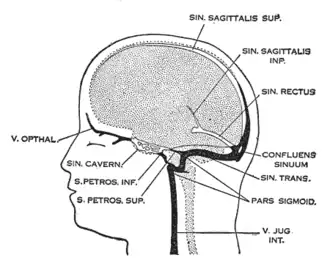

| Dural veins | |

Pathogenesis

The veins of the brain, both the superficial veins and the deep venous system, empty into the dural venous sinuses, which carry blood back to the jugular vein and thence to the heart. In cerebral venous thrombosis, blood clots usually form both in the veins of the brain and the venous sinuses. The thrombosis of the veins themselves causes venous infarction (damage to brain tissue due to a congested and therefore insufficient blood supply). This results in cerebral edema (both vasogenic and cytotoxic edema), and leads to small petechial haemorrhages that may merge into large haematomas. Thrombosis of the sinuses is the main mechanism behind the increase in intracranial pressure due to decreased resorption of cerebrospinal fluid (CSF). The condition does not typically lead to hydrocephalus, however, because there is no difference in pressure between various parts of the brain.[3] However, those who have deep cerebral venous sinus thrombosis or oedema at basal ganglia are more prone to hydrocephalus development.[13]